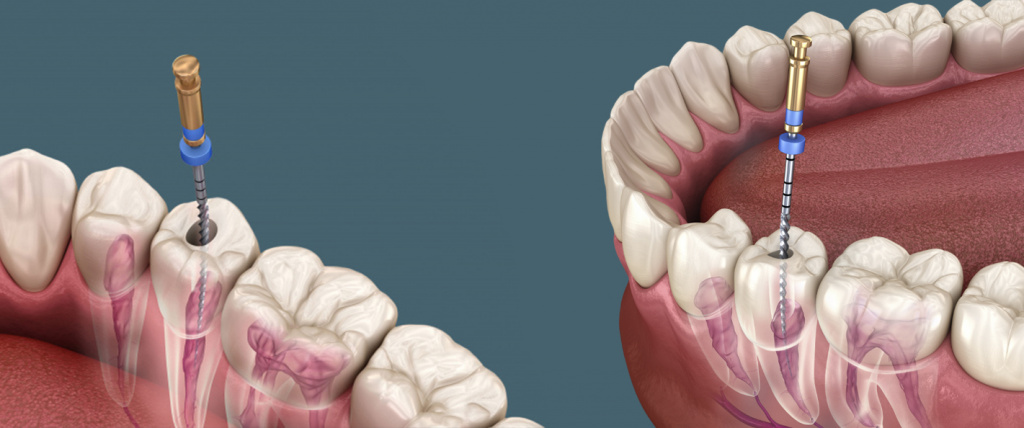

Этапы лечения корневых каналов

Во время второго визита в клинику временная пломба извлекается, производится экстирпация пульпы. Доктор приступает к механической обработке корневых каналов: расширяет их, придает конусовидную форму. Диаметр каналов до обработки равен долям миллиметра. Разумеется, качественно очистить и запломбировать их невозможно. Механическая обработка позволяет создать оптимальные условия для герметизации каналов и купирования воспалительного процесса. Затем приступают к медикаментозной обработке каналов антисептическими препаратами. На данном этапе уничтожаются патогенные микроорганизмы, каналы очищаются от остатков некротизированной пульпы и дентинных опилок. Следующий этап – установка штифта и пломбирование каналов. Необходимо добиться их полной герметизации. Пломбировочным составом заполняется также и полость коронковой части зуба.